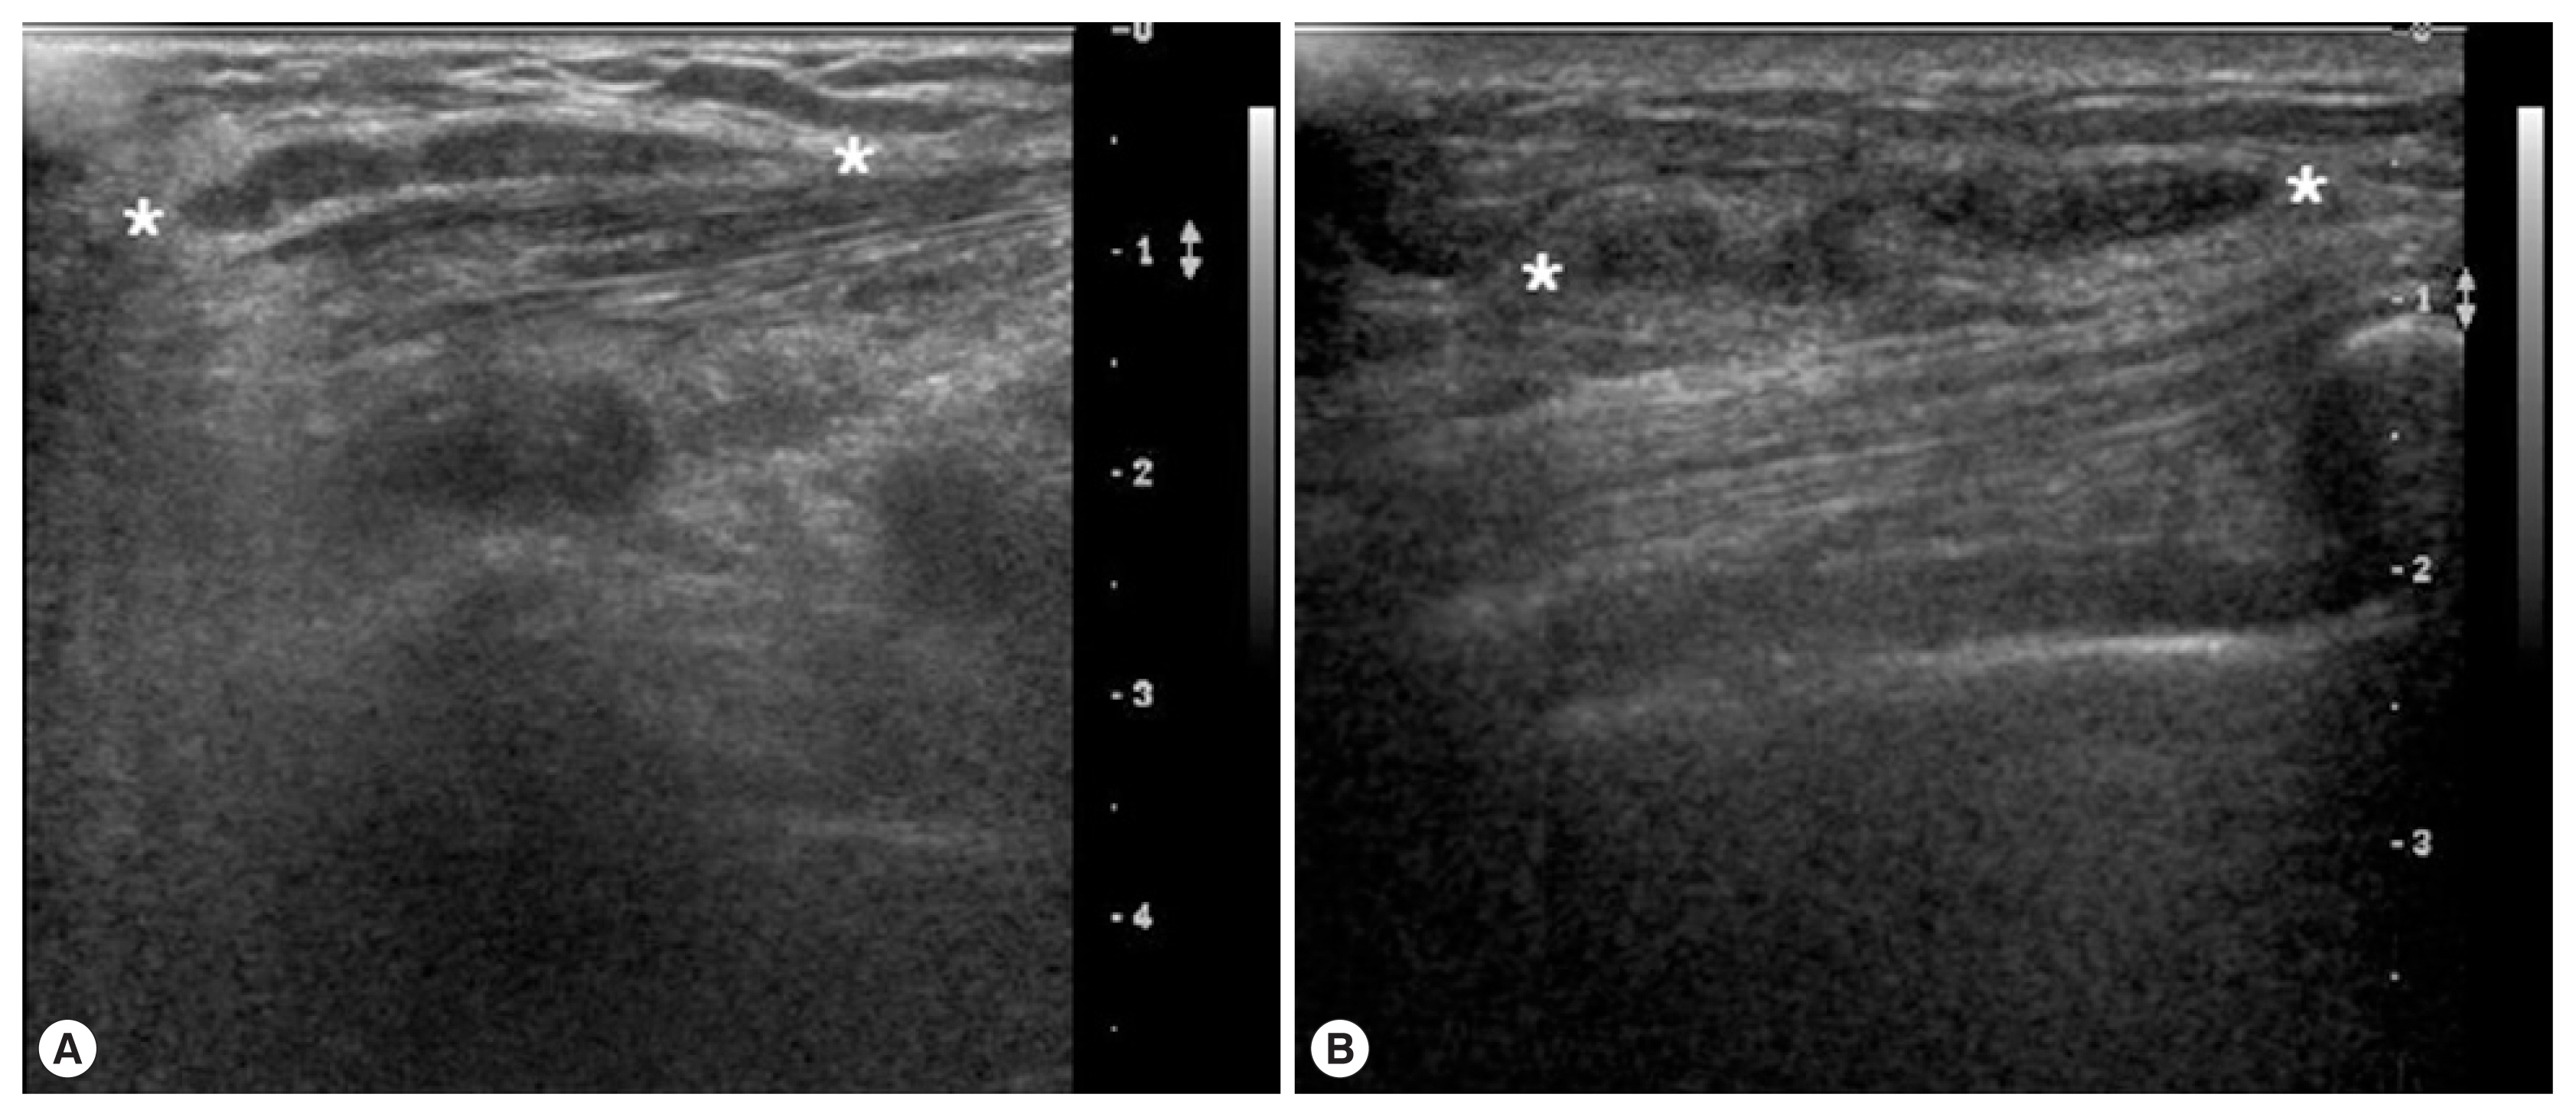

A 69-year-old woman presented with a painless mass of the left upper breast. The mass was palpable 3 weeks prior to presentation. The patient was first treated with acupuncture at another hospital. The patient had no underlying disease other than hypertension. She denied any family history. The patient also denied eating raw foods, including snakes and frogs, although she did enjoy eating Korean-style raw beef from time to time. The patient did not complain of pain or pruritus at the lesion site. Although the mass had been palpable for 3 weeks, it was not palpable 3 days prior to visit. On physical examination, there was no mass found on the breast. There were no specific findings on other parts of the body. Laboratory findings were as follows: hemoglobin of 13.1 g/dl and white blood cell (WBC) count of 6,510/μl (neutrophil 42.0%, eosinophil 5.0%). Chest X-ray and electrocardiogram (ECG) findings were normal. Mammography showed only benign calcifications of the left breast. On breast ultrasonography, a tubular hypoechoic lesion was seen at the subcutaneous fat layer in the left upper outer quadrant of the breast. The tip was connected to the back of the pectoral major muscle (Fig. 1A). A parasitic infection of the breast was suspected, and excisional biopsy was performed. During the operation, a worm surrounded by membranes located between the pectoral muscles was visually identified and removed (Fig. 2). The color of the identified worm was white. Its shape was thin and long, with a length of 30 cm and an outer diameter of 0.3 cm (Fig. 3A). Pathological examination demonstrated characteristic features of sparganum, including tegumental brush border, bundles of longitudinal muscle fibers, and lack of a gastrointestinal tract (Fig. 4A, B). Her postoperative course was uneventful. Follow-up was performed for one month postoperatively. No specific findings were observed.

A 46-year-old woman presented with a painless mass of the right breast. The mass was palpated 4 months prior to presentation. The patient was followed up without any special treatment. She presented to the hospital because of recent increase in size of the lesion. The patient was taking medication for angina symptoms. She had no other underlying diseases. There were no specific findings in her family history. She denied of any recent consumption of raw food. The patient did not complain of pain, pruritus, or other symptoms in association with the lesion. She did not complain of any particular symptoms in other parts of the body. On physical examination, a 2 cm sized painless mass in the right upper part of the breast had grown in size compared to her last visit. The mass was hard and well-defined. There was no visual skin depression or color change. Laboratory findings were as follows: hemoglobin of 11.7 g/dl and WBC count of 5,230/μl (neutrophil 35.5%, eosinophil 3.1%). Chest X-ray and ECG findings were normal. On mammography, there was no specific finding other than an asymmetric hyperdense lesion on the right upper side of the breast. A hypoechoic tubular lesion was observed on breast ultrasonography (Fig. 1B). A parasitic infection of the breast was suspected, and excisional biopsy was performed. During the operation, white circular figures filling the inside of the mass were visible. Length and outer diameter were 16 cm and 0.2 cm, respectively (Fig. 3B). Pathologic examination of the tissue surrounding the worm showed chronic granulomatous inflammation accompanied by necrosis. The worm was confirmed as sparganum and microscopic findings showed characteristic thick eosinophilic tegument, subtegumental calcareous bodies, and longitudinal strips of muscles (Fig. 4C, D). Follow-up was done for up to 13 months postoperatively. No specific findings were observed during follow-up.

If breast sparganosis is suspected through review of patient’s medical history and physical examination, mammography and breast ultrasonography can be used to help diagnose it. On mammography, the mass appears as an irregular soft tissue-density mass with clear margins without calcification. On ultrasonography, the sparganum body is observed as a hypoechoic structure inside a heterogeneous hyperechoic mass. The empty tract has a hypoechoic structure of similar shape. Granulation tissue around these structures is observed as a hyperechoic mass [5]. In the reported cases here, mammography alone is not enough to suspect parasite infection. It is through the detection of a tubular structure by breast ultrasonography that we were able to clinically suspect parasitic infection. Enzyme-linked immunosorbent assay (ELISA) test using antigens of plerocercoids can be used for the serodiagnosis of sparganosis. ELISA has a high sensitivity for detecting serum anti-sparganum antibodies in humans, but the main disadvantage is that cross-reactions with other parasitic diseases are possible [17]. Confirmation of sparganosis can be done surgically, and in both of the reported cases of this study, sparganum was easily confirmed with the naked eyes because its shape was preserved during surgery. Surgical treatment of sparganosis is a fundamental and effective treatment. Drugs such as praziquantel are sometimes administered alongside the surgical excision of the sparganum [18]. There are a few cases of recurrence after surgical removal of the sparganum [19]. Infection of sparganum can be prevented by avoiding eating raw snakes and frogs without drinking contaminated beverages.